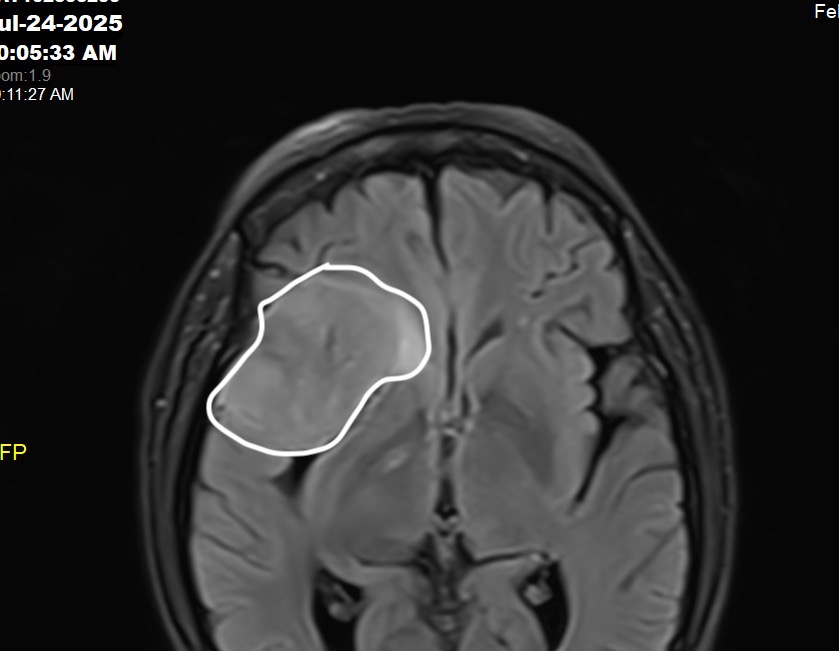

The tumor wasn’t just large. He called it gigantic. A 5 cm tumor the size of her fist or a potato.

Sitting behind her right eye, dangerously close to her optic nerve.

"We need to get this out before you start having symptoms," he said. "You're at high risk for seizures."